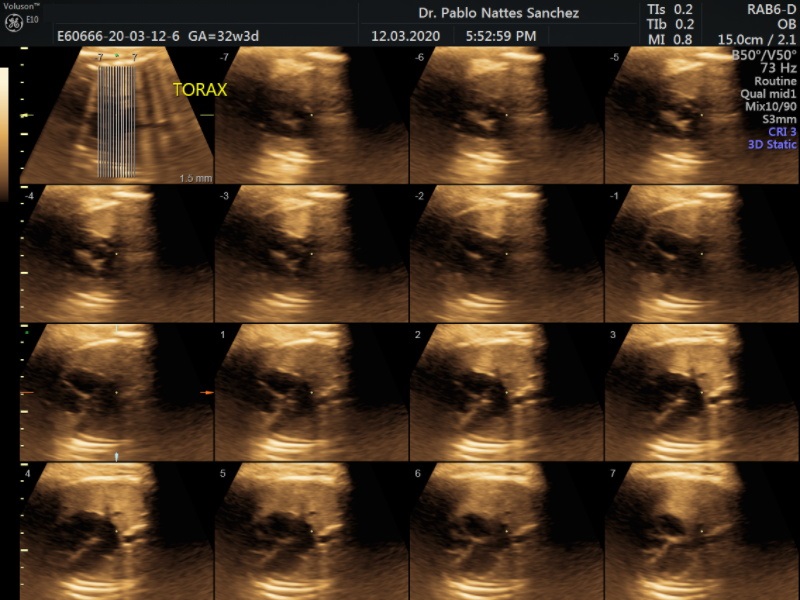

• Son exámenes especiales enfocados al estudio detallado del corazón y cerebro fetal.

• El estudio esta direccionado a fetos con elevado riesgo de malformación cardiaca o cerebral.

• Se emplean todas las técnicas de exploración ecográfica 3D, 4D y Doppler y se realiza generalmente por via abdominal, sin embargo dependiendo de la posición fetal en algunas oportunidades estos exámenes fetales son complementados con ecografía vía trans vaginal.